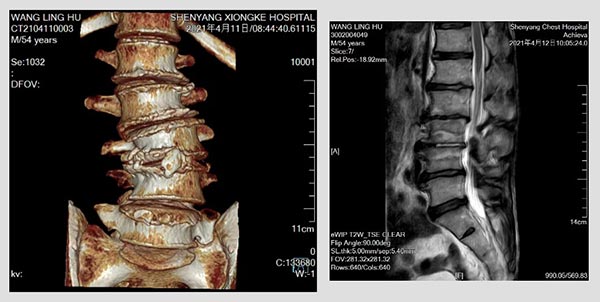

55岁的老王被腰腿痛麻困扰了近十年。十年来四处求医,病情却未得到缓解,反而越来越重。9个月前老王自己感觉疼痛已经无法忍受,下地行走困难,夜不能能昧,病情加剧生活都无法自理。最后来到沈阳市第十人民医院骨一科找到柳盛春主任,陆续完善脊柱全长正侧位,颈胸腰椎磁共振等检查后,柳主任发现患者神经根性症状及浅感觉减退范围同腰椎轴性痛等体征混杂在一起,与影像学资料不符,这给诊断带来了巨大的困难。经反复的病情研究,细致的查体,最后柳主任认为老王得的是退变性腰椎侧凸。

OLIF融合器及椎弓根螺钉置入后影像